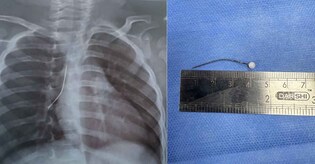

The child was rushed to the VPS Lakeshore Hospital's emergency room in severe respiratory distress.

When foreign objects enter the human body and get stuck there for extended periods, it can be hazardous.